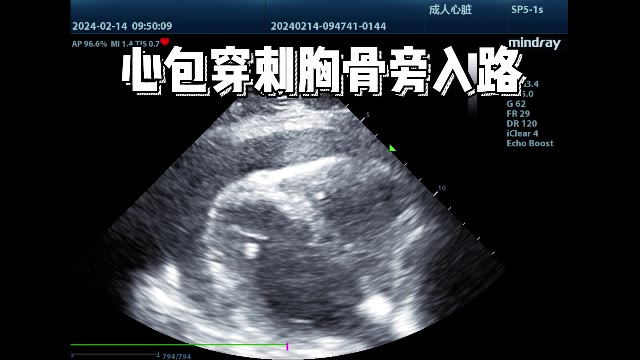

3、胸骨旁入路:(通常右室前壁心包积液偏少,不作为首选)